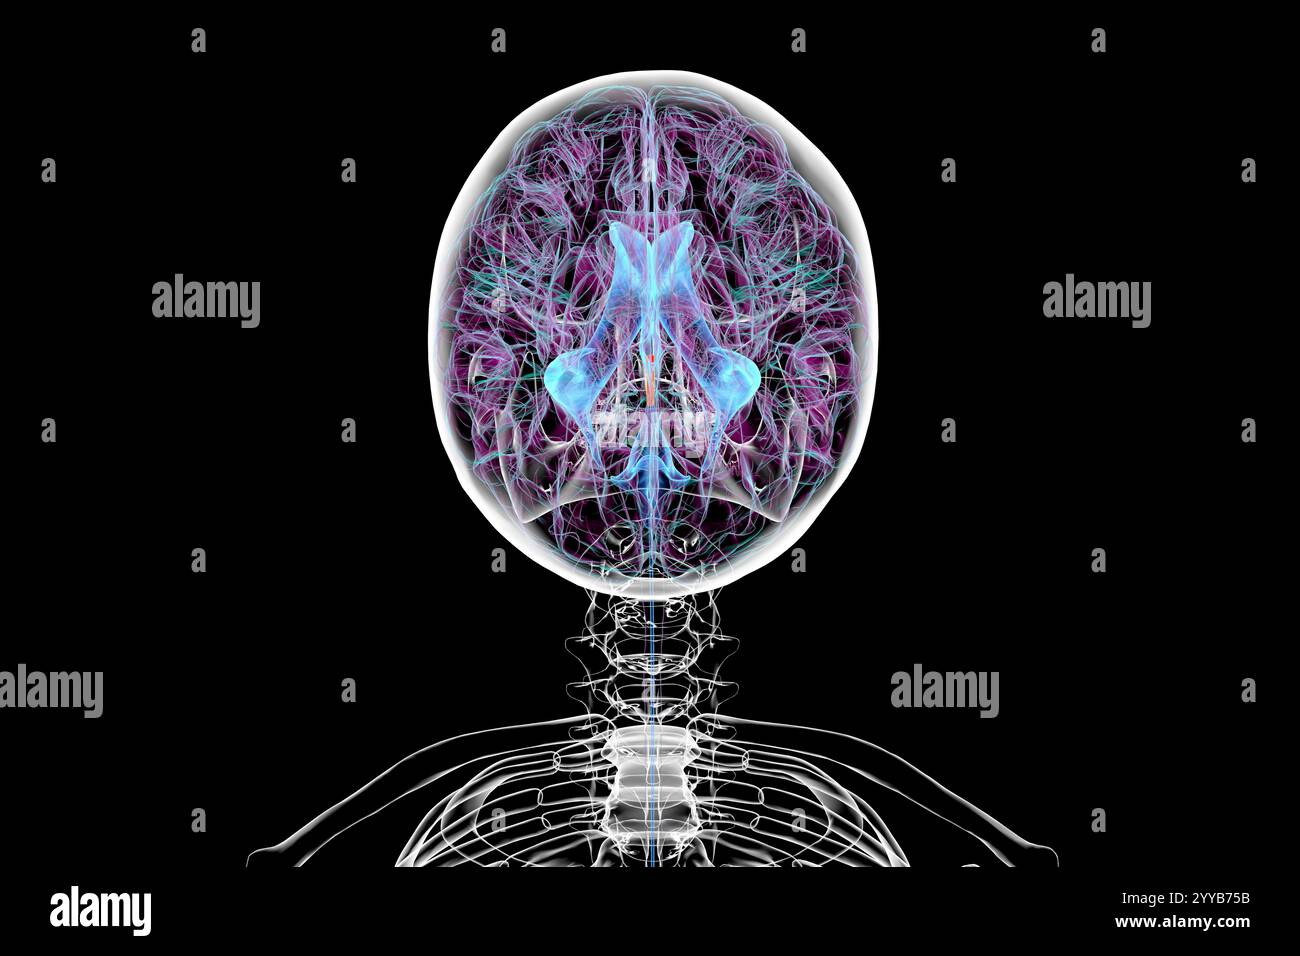

RF3C7H8A8–Abbildung des Gehirns mit hervorgehobenem Aquädukt (rot) und ventrikulärem System (blau), Darstellung des Liquorflusses.

RF3C7H8A6–Abbildung des Gehirns mit hervorgehobenem Aquädukt (rot) und ventrikulärem System (blau), Darstellung des Liquorflusses.

RF3C7H8AA–Abbildung des Gehirns mit hervorgehobenem Aquädukt (rot) und ventrikulärem System (blau), Darstellung des Liquorflusses.

RF3C7H8AF–Abbildung des Gehirns mit hervorgehobenem Aquädukt (rot) und ventrikulärem System (blau), Darstellung des Liquorflusses.

RF3C7H8A3–Abbildung des Gehirns mit hervorgehobenem Aquädukt (rot) und ventrikulärem System (blau), Darstellung des Liquorflusses.

RF2YYB746–Computerdarstellung des menschlichen Gehirns mit orangefarbenem Aquädukt und grünem Ventrikelsystem mit Liquorfluss.

RF2YYB74E–Computerdarstellung des menschlichen Gehirns mit orangefarbenem Aquädukt und grünem Ventrikelsystem mit Liquorfluss.

RF2YYB751–Computerdarstellung des cerebralen Aquädukts (orange), eines schmalen Kanals im Mittelhirn, der den dritten und vierten Ventrikel verbindet und den Liquorfluss erleichtert.

RF2YYB74X–Computerdarstellung des cerebralen Aquädukts (orange), eines schmalen Kanals im Mittelhirn, der den dritten und vierten Ventrikel verbindet und den Liquorfluss erleichtert.

RF2YYB75A–Computerdarstellung des cerebralen Aquädukts (orange), eines schmalen Kanals im Mittelhirn, der den dritten und vierten Ventrikel verbindet und den Liquorfluss erleichtert.

RF2YYB741–Computerdarstellung des menschlichen Gehirns mit orangefarbenem Aquädukt und grünem Ventrikelsystem mit Liquorfluss.

RF2YYB742–Computerdarstellung des menschlichen Gehirns mit orangefarbenem Aquädukt und grünem Ventrikelsystem mit Liquorfluss.

RF2YYB754–Computerdarstellung des cerebralen Aquädukts (orange), eines schmalen Kanals im Mittelhirn, der den dritten und vierten Ventrikel verbindet und den Liquorfluss erleichtert.

RF2YYB75B–Computerdarstellung des cerebralen Aquädukts (orange), eines schmalen Kanals im Mittelhirn, der den dritten und vierten Ventrikel verbindet und den Liquorfluss erleichtert.

RF2YYB759–Computerdarstellung des cerebralen Aquädukts (orange), eines schmalen Kanals im Mittelhirn, der den dritten und vierten Ventrikel verbindet und den Liquorfluss erleichtert.

RF2YYB740–Computerdarstellung des menschlichen Gehirns mit orangefarbenem Aquädukt und grünem Ventrikelsystem mit Liquorfluss. Rückansicht.

RF2YYB755–Computerdarstellung des cerebralen Aquädukts (orange), eines schmalen Kanals im Mittelhirn, der den dritten und vierten Ventrikel verbindet und den Liquorfluss erleichtert. Rückansicht.

RM2CE564C–. Erkrankungen des Nervensystems . Abb. 43. – Basis der Braix axd Hirnnerven. Sucht nach ihren Hauptabteilungen im Menschen, der Korpora quadrigemina (siehe Abb. 44und 45) oben die Spalte von Sylvius unten, und darunter die Fasermasse der oberen Pedunkles des Kleinhirns und der Pedunculi cerebri (Abb. 46, 47, 48, 49). Seine Kerne (Neuronenzellen) liegen entlang der gesamten Länge des Aquädukts von Sylvius, von seinem frontalen Ursprung fast bis zu seinem kaudalen Ende;5 52 HISTOLOGIE DES ZENTRALNERVENSYSTEMS die Kerne der trochlearen Nerven liegen posteriorly dort, wo der aque-Ductus liegt

RF2YYB752–Computerdarstellung des cerebralen Aquädukts (orange), eines schmalen Kanals im Mittelhirn, der den dritten und vierten Ventrikel verbindet und den Liquorfluss erleichtert. Rückansicht.

RF2YYB75E–Computerdarstellung des cerebralen Aquädukts (orange), eines schmalen Kanals im Mittelhirn, der den dritten und vierten Ventrikel verbindet und den Liquorfluss erleichtert. Ansicht von unten.